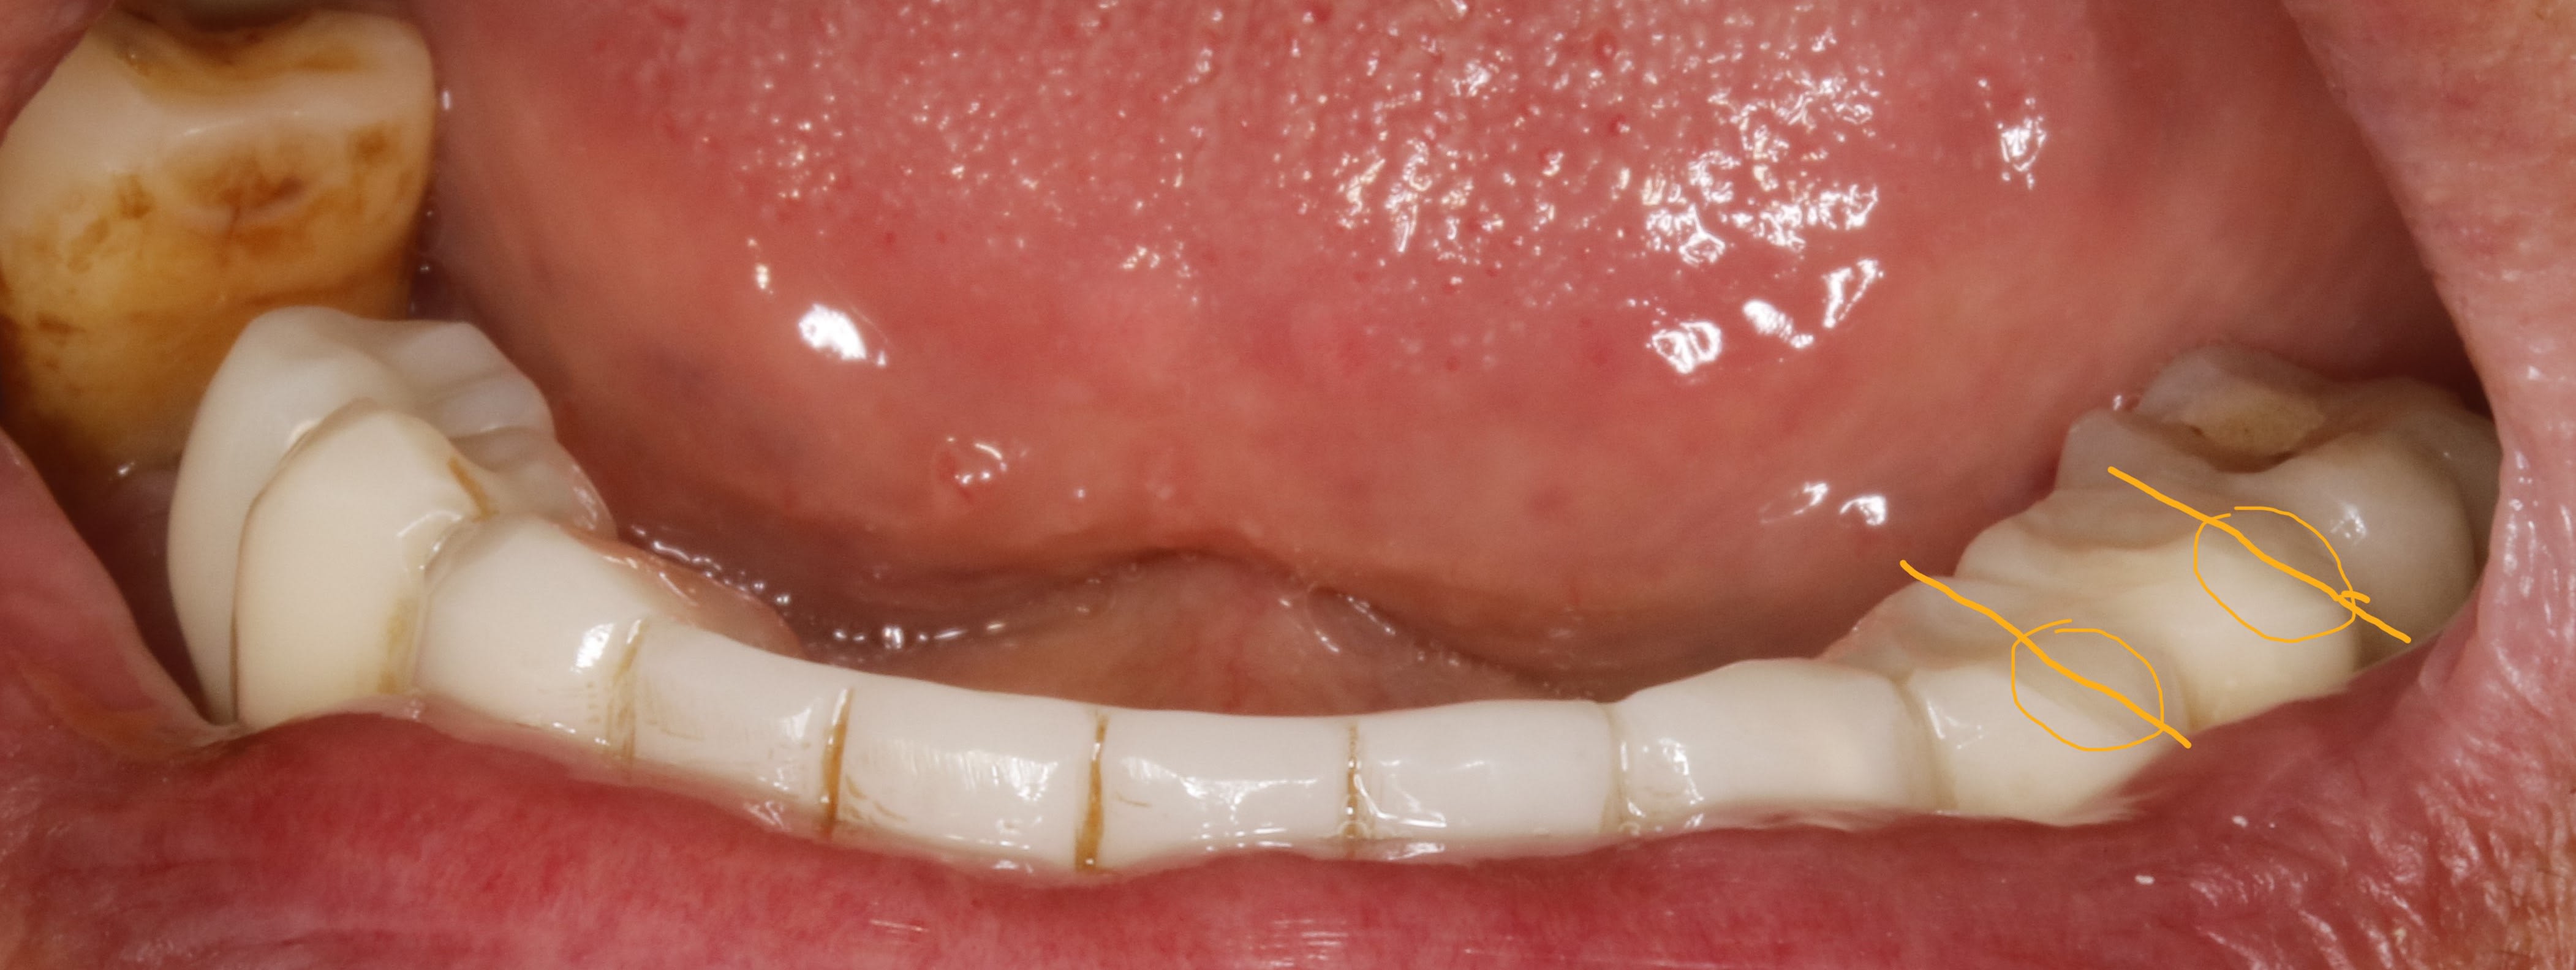

bon , revenons à notre affaire , quel rapport entre la conicité et l occlusion ? .

le rapport le voilà , je remets ici la photo du prov au bout de 3 mois , avec les traits orange .

de toute évidence il y a des faces d usure à gauche qu il n y a pas à droite .

donc même sans parler pb occlusal , si je veux faire la prothèse , il faudra au minimum que je sois homothétique à ces pistes .

ce qui va m obliger à rentrer les moignons en lingual . pcq de toute évidence , lui il n a qu une envie c est d aller à gauche . et s il y est allé avec les prov , il y retournera avec les vrais

ou alors on peu aussi anticiper en vestibulant le haut , mais on ne va pas s amuser à casser le haut , meme s il le faudrait effectivement .

dejà ca répond à Prunelles et Bouboule , pourquoi 3 mois ? bin rien que pour ça ça vaut le coup .

maintenant regardes bien la photo vue de haut que je remets .tu le vois le trait gris ?

c est l alignement de la ligne de crête . et cà c est fondamental pcq c est ce qui préfigure la courbe de Wilson et Monson .

c est ce qui fait qu il y aura une stabilité ou pas .

( on ne va pas rentrer dans les détails d' occlusos mais là tu peux me croire pcq la seule explication moderne retenue quant à l utilité de Wilson et Monson c est ma théorie . publication dans les EMC , mais aussi les gala et ici Paris des revues d ortho , et + encore.)

bref , le fait d aligner les sommets va t obliger à incliner les moignons si besoin .

elle vient de là la conicité du bordel global . :-)

et non pas d ailleurs , ce n est pas un choix de style de taille , c est une obligation architecturale .